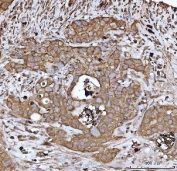

HBEGF Antibody Appendiceal Adenocarcinoma IHC. Immunohistochemistry analysis of FFPE human appendiceal adenocarcinoma tissue stained with HBEGF antibody detecting Heparin-binding EGF-like growth factor (DT-R). Tumor epithelial cells show membranous and cytoplasmic staining, consistent with localization of HBEGF as a cell surface receptor involved in diphtheria toxin binding and receptor-mediated internalization, as well as EGFR ligand signaling. The staining outlines glandular tumor structures, while surrounding stromal components show comparatively reduced signal. Hematoxylin counterstain highlights nuclei in blue. HIER: boil tissue sections in pH 8 EDTA for 20 min and allow to cool before testing.